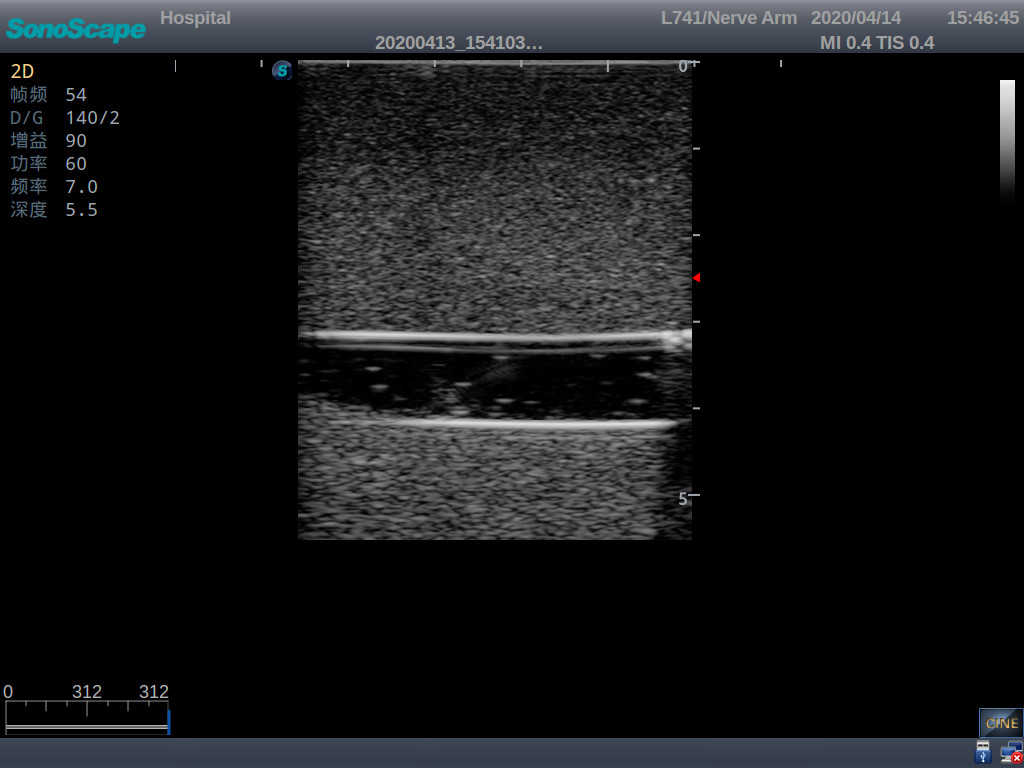

PICC Ultrasound Training Model

Model TYE1510.1

It is a model covering up from lobulus auriculae plane to the umbilical plane, and it has anatomical structures like clavicle, rib, sternocleidomastoid, jugular vein and basilic vein.

1)   Made of high molecular polymer ultrasound material, close to the real skin

2)   It can be used by real ultrasound machines

3)   Clear and real images of the tissues and organs (basilic vein and superior vena cava)

5)   Observe the guide wire marches

6)   Detect whether the catheter is properly placed